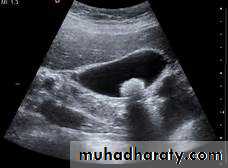

Ultrasound

• US imaging uses ultra-high-frequency sound waves to produce cross-sectional images of the body.• The basic component of the US probe is the piezoelectric crystal.

• Hyperechoic or hypoechoic or anechoic.

US scanning is applicable to:

• Solid organs, including liver, kidneys, spleen and pancreas.

• Urinary tract.

• Obstetrics and gynecology.

• Small organs including thyroid and testes.

• Breast.

• Musculoskeletal system.

• US-guided biopsy of various body cavities and organs.

• Transvaginal US (TVUS): accurate assessment of gynecological problems and of early pregnancy up to about 12 weeks’ gestation

• Transrectal US (TRUS): guidance of prostate biopsy; staging of rectal cancer

• Transcranial US: neonatal brain and TCD.

• Endoscopic US (EUS): assessment of tumors of the upper gastrointestinal tract and pancreas

• Transoesophageal echocardiography (TOE): TOE removes the problem of overlying ribs and lung, which can obscure the heart and aorta when performing conventional echocardiography.